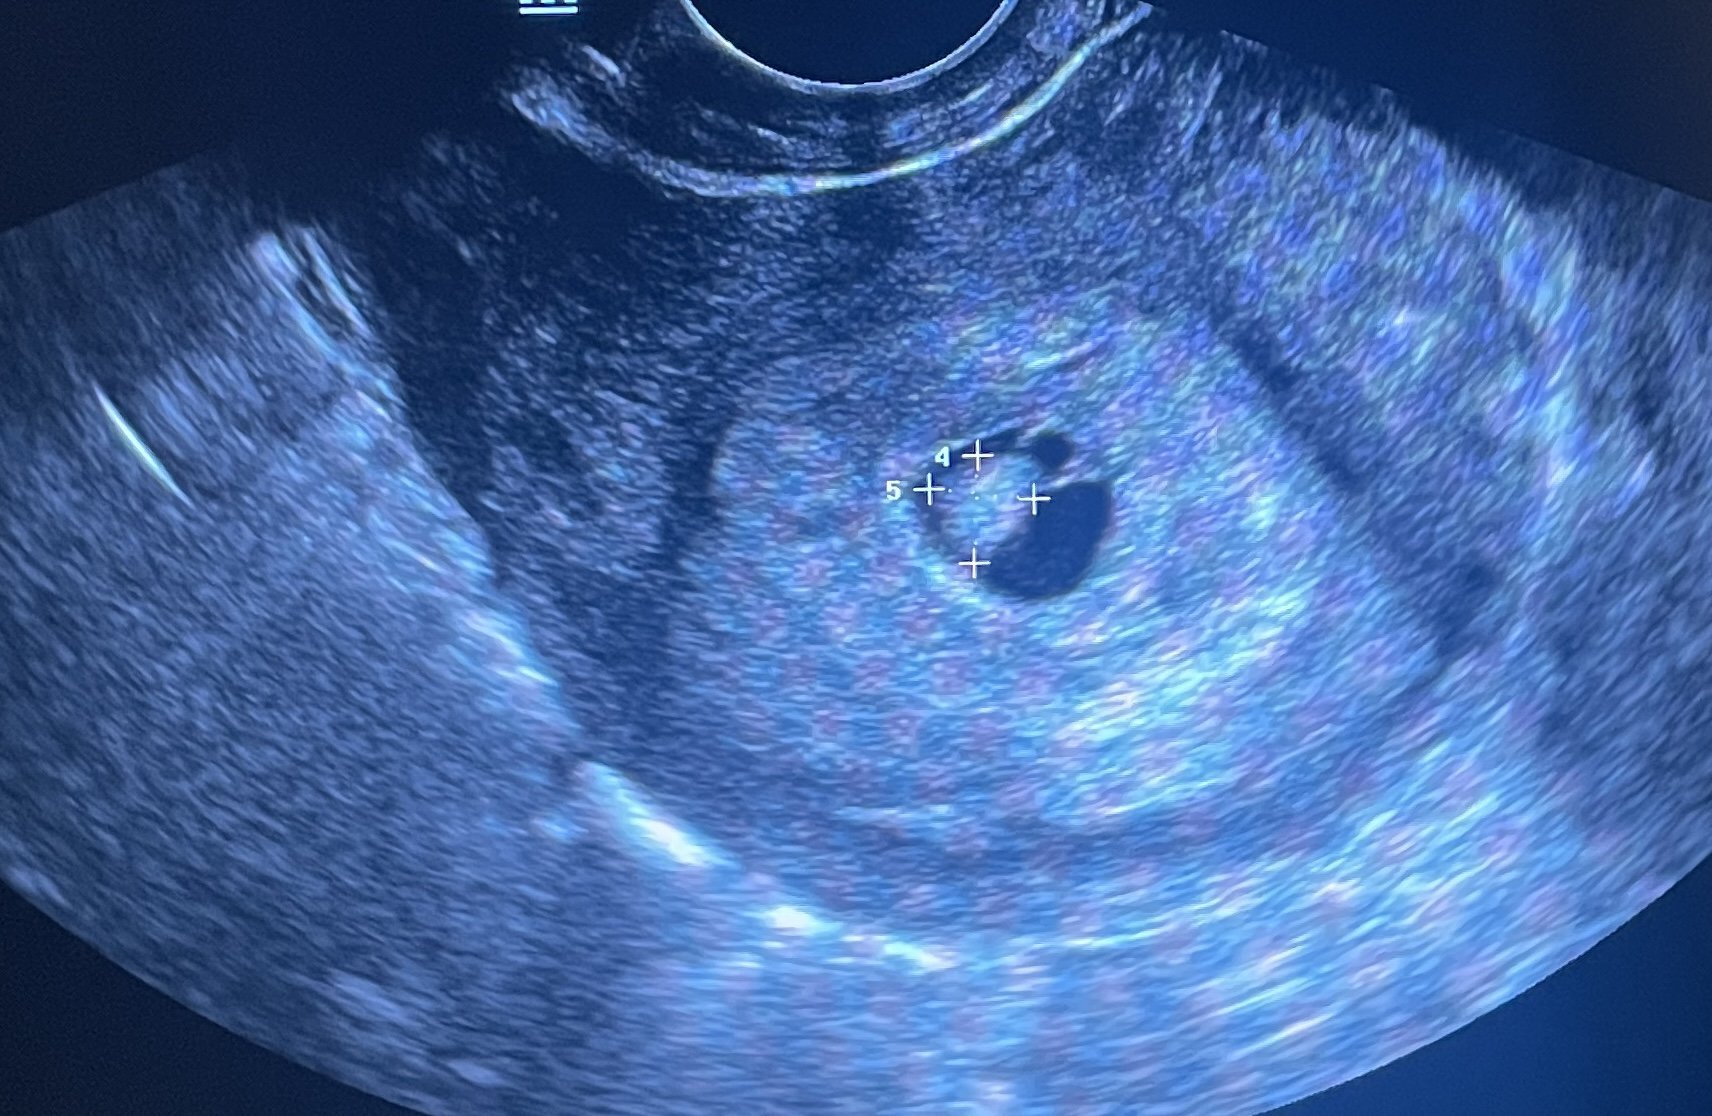

Какво представляват белите точки в плодния сак на ехографската снимка?

Какво представляват черните точки в матката на ехографската снимка?